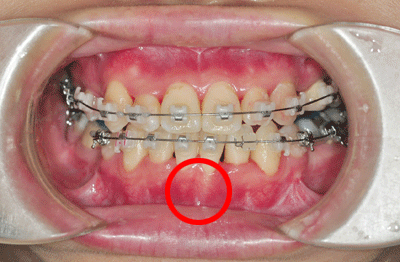

▼문제라고 생각되는 아랫니 뿌리. 희끄무레하게 비치는 게 보이지요.▼

그나마 400픽셀로 줄여서 이 정도지, 이 새벽에 원본 2000픽셀로 보면 무섭습니다.